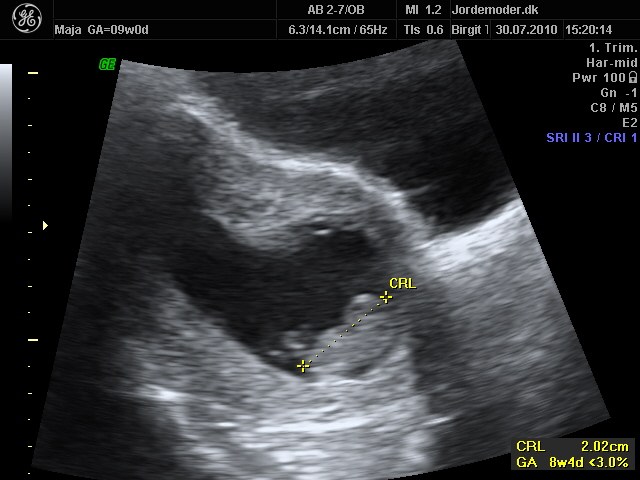

jeg var til scanning lige der omkring og det var en indvændig scanning... fik afvide det ikke var meget man kunne se på en udvændig scanning så tidligt

Jeg var til udvendig scanning 7+6, der kunne man se alt hvad man skulle se.

Den læge, der scannede mig, sagde det slet ikke var nødvendigt med indvendig scanning, men han er altså også meget erfaren.